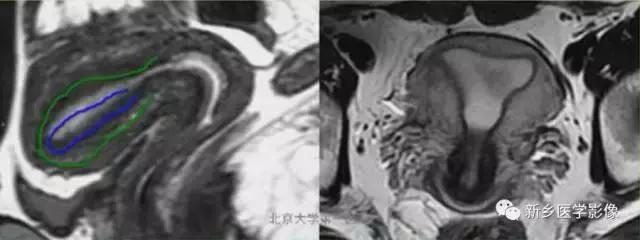

II:单角子宫:

子宫单角,呈香焦形。伴或不伴残角,残角体积小,可存在内膜腔,可同外界相通。

1、有宫内膜腔的残角,与单角子宫相通。

2、有宫内膜腔的残角,不与单角子宫相通。

3、残角内无内膜腔。

4、无残角。

上图:单角子宫(II-B残角,有内膜腔,不相通):右侧残角宫腔内积血,为短T1长T2异常信号。左侧单角子宫,见带状结构,呈香蕉样。

上图:II-D无残角:右侧单角子宫,左侧无残角